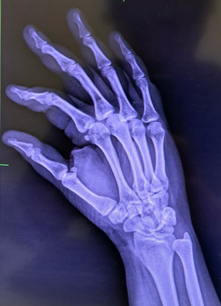

A 39-year-old Asian female develops a blister, at the site of a cannula inserted for hydration with normal saline. The lady had a recent history of dehydration due to an outdoor summer lunch on a hot day. Her past medical history includes Ulcerative Colitis, Psoriasis, and Psoriatic arthritis for the last decade. The large blister ruptured, exposing the underlying dermis. She was prescribed saline washes with application of Fusidic acid ointment, twice daily (Figure 1). The lesion responded initially, but after two weeks, the edges of the lesion became hard, indurated and crusted and the underlying dermis showed a darkened pigmentation with pain on palpation of the snuff box underneath. A preliminary clinical diagnosis of superficial venous thrombosis was proposed; but refuted when the coagulation studies and INR appeared normal. A trial of an ointment containing hydrocortisone, Neomycin, Bacitracin, and Polymyxin for local application, and oral Vibramycin failed to show any improvement in closing the wound, or receding the central black pigmentation, and the patient continued to complain of wrist pain. An X-ray revealed local bone lucency under the lesion (Figure 2). A surgical consult was requested that excavated the necrotic tissue and closed the edges neatly by eleven stiches in local anesthesia administered to the patient (Figure 3 & 4).

Figure 2 Xray of hand revealing a local bone lucency at the region beneath the blister formation.